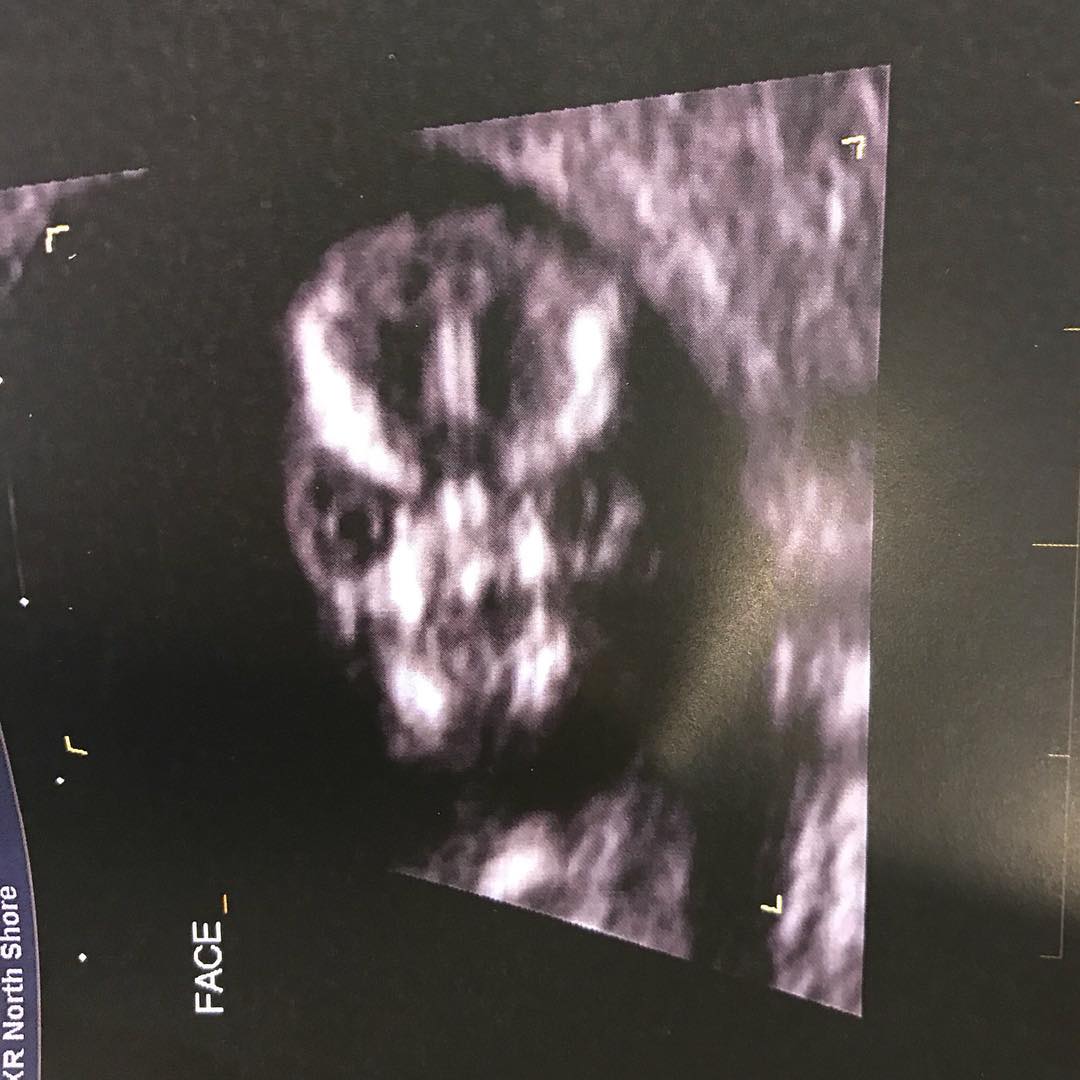

Жительница Австралии поделилась в Twitter фотографией УЗИ своего будущего ребенка, которого пользователи сети сравнили с Волан-де-Мортом.

«Мой врач решил сделать снимок моего ребенка в анфас, и это самое стремное, что я видела в своей чертовой жизни», — прокомментировала Шарни Тернер снимок в Twitter.

Пользователи Twitter в шутку предположили, что девушка ждет не просто ребенка. Кто-то сравнивает его лицо с лицом трансформера, а кто-то — с персонажем из фильма «Синистер». Другие и вовсе предположили, что девушка ждет Волан-де-Морта.